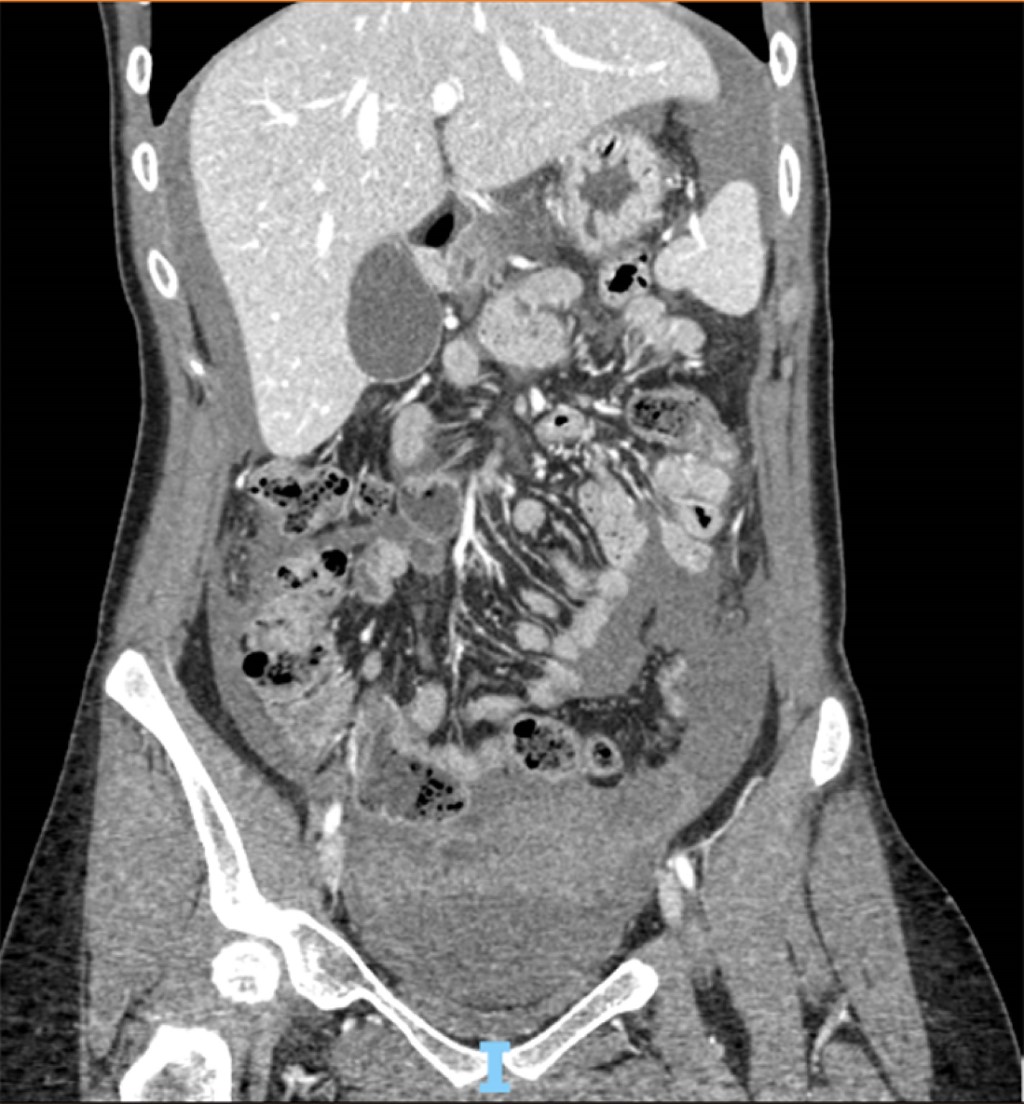

La imagen tomográfica presentada es de una paciente de 24 años de edad sin antecedentes patológicos, la cual se sometió a colocación de dispositivo intrauterino y fue dada de alta, pero posteriormente ingresó al servicio de urgencias 24 horas después con un cuadro de dolor abdominal agudo y datos consistentes con choque hipovolémico tipo hemorrágico grado II. Asimismo, a la exploración abdominal se encontró un abdomen rígido, con defensa involuntaria y doloroso a la palpación. Durante su valoración se encontró con niveles de hemoglobina de 9.16 g/dL, hematocrito de 28.3%, leucocitosis de 9.14 × 103/µL, plaquetas 198 × 103/µL. La tomografía (Figura 1) muestra abundante líquido libre en cavidad abdominal de localización perihepática, periesplénica y ambas correderas parietocólicas, así como en cara anterior y posterior del útero sugestivos de hemoperitoneo.

Figura 1